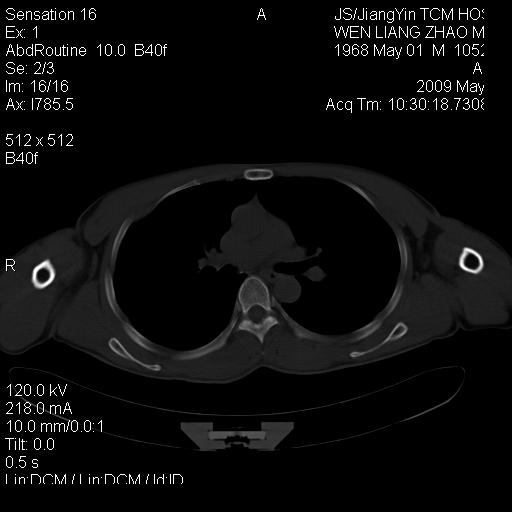

标题: CT19762:左侧喙突处压痛二年。考虑骨样骨瘤。 [打印本页]

标题: CT19762:左侧喙突处压痛二年。考虑骨样骨瘤。

左侧喙突处压痛二年。考虑骨样骨瘤。

病灶外缘膨胀明显,灶缘硬化较少,结合病史较符合骨母细胞瘤,其他亦不排除如软骨及软骨母细胞瘤等(病灶形态,成份较符合,发病部位也符合,只是年龄较大),骨样骨瘤多有较明显的自发性痛,且夜间痛明显,病史为压痛两年,不太符合.